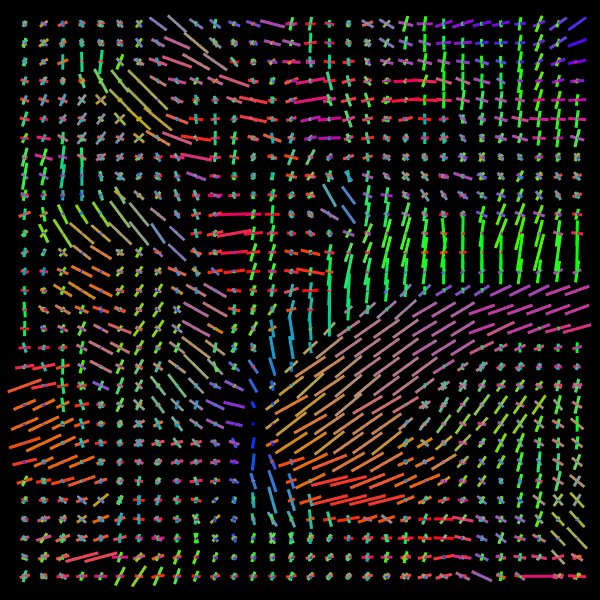

Training stage. We compare the results of the proposed Voxel (VOX) and Neighborhood (NBH) models with two of the SOTA methods which tackle the same task: Diffusion Basis Functions (NNLS) proposed by Ramirez-Manzanares et al. (2007)) and Constrained Spherical Deconvolution (CSD) proposed by Tournier et al. (2007). There are many options to compare distributions, a common comparisson procedure used in this context is to detect peaks and compute the angular error between the real peaks and the estimated ones. However, to compare modes in not a standard procedure for comparing distributions. Among them two notable options are Kullback-Leibler (KL) Divergence and the Wasserstein Distance (also know as the Earth Mover Distance, EMD). Despite its computational cost, EMD has shown to represents more precisely the distribution distance (Levina and Bickel, 2001; Aranda et al., 2011; Arjovsky et al., 2017). EMD represents the minimum cost of transforming a peak distribution into another, weighting by angle. We create a synthetic dataset with gradient table of the Stanford HARDI dataset (Rokem et al., 2015), the eigenvalues of a Diffusion Tensor model fitted to the corpus callosum region, and the SNR computed in such a data (Descoteaux et al., 2011). The estimated SNR depends on image region: most of the measures laid into [20,24]2024[20,24], so we randomly generate data selecting the SNR into [20,30]2030[20,30]. Figure 5 depicts the error for each analyzed model. The vertical axis corresponds to the angle (θ1subscript𝜃1\theta_{1}) between the first PDD and the second one. Meanwhile, the horizontal axis shows the angle between the third PDD and the plane formed by the first two PDDs. The dynamic range of the error maps shows a better performance of the proposed models. We select some predictions for a visual inspection (qualitatively comparison). For illustration purposes, we choose one between the top–101010 and one of the bottom–101010 according to its EMD values for the studied models: VOX, NBH, NNLS, and CSD. The results are presented in Figure 6. The first two columns correspond to the best predictions: the first column shows the target and the second column shows the prediction. The third and fourth columns follow the same order but for the worst predictions. Arrows illustrate the generated PDDs (ground truth). According to the α𝛼\alpha value: blue, orange, and green were used for the first, second, and third PDD, respectively.

Refer to caption

Figure 6: Predicted voxels with lowest (first two columns) and highest error (last two columns).